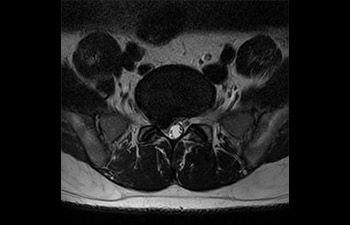

Pelvis image

Pelvis de mujer con mioma

con Compressed SENSE